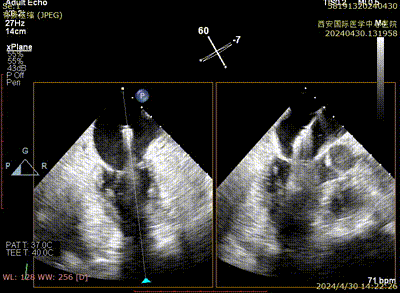

二尖瓣夹夹闭

术后二尖瓣反流评估

术后结果

心脏瓣膜介入团队术中在2区植入一枚二尖瓣夹,关闭二尖瓣夹时时刻关注瓣叶张力,并随时释放张力。患者术后反流降至1+,跨瓣压差为3mmHg。